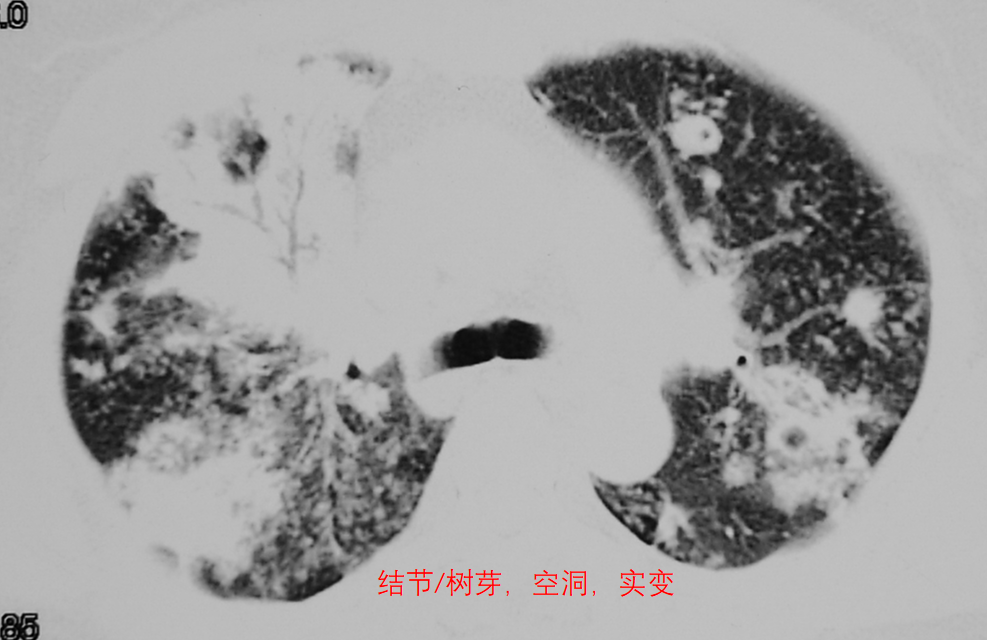

簇状分布的小叶中心性微结节、新旧不均,可伴树芽征或空洞。

在肺结核的胸部CT上我们经常见到许多微结节形成树芽症。除此之外,在实变比较明显的部位,仔细看它的边缘部分,往往也能找到一些微结节和树芽(箭头),有些还可以形成空洞。

这张CT显示的是经支气管播散的肺结核的典型表现:簇状分布的小叶中心性微结节、新旧不均: